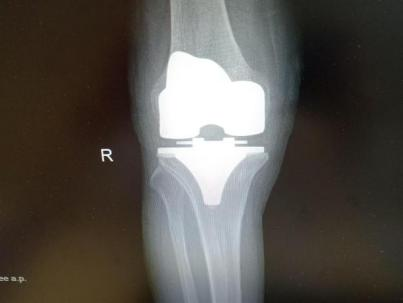

12月17日,贵州航天医院第88次晨读会由我院骨一科主任、副主任医师陈明勇作学术交流,他以“肱骨近端骨折并肩关节脱位的手术治疗”为题,全面讲解了该损伤的手术策略、术中血供保护理念及内侧支撑重建技术等内容,并通过多个典型病例图文资料分享了从损伤机制分析、手术步骤实施到术后随访评估的完整过程与关键细节,为临床处理此类复杂骨折提供了较为全面的技术参考,有助于在手术规划中结合个体情况开展针对性治疗。 贵州航天医院 骨科专家简介 陈明勇 骨一科主任,副主任医师 临床擅长:从事创伤骨科工作约20年,对骨缺损、骨不连、骨肿瘤、肢体畸形等的肢体矫形重建及功能重建,慢性化脓性骨髓炎的根治治疗、糖尿病足的保肢治疗、快速康复理念(ERAS)下的老年骨折的诊治,四肢复杂骨折的诊治,四肢骨折等微创手术治疗具有丰富的临床经验。 2004年毕业于遵义医学院临床专业,曾在中国人民解放军总医院、广西医科大学第一附属医院、上海第六人民医院骨科进修。中国中西医结合学会骨伤科专业委员会横向骨搬移治疗糖尿病足及微血管网再生学组首届委员,遵义市医学会创伤分会常务委员。 瞿 晖 骨科党支部书记,骨二科主任,副主任医师 临床擅长:对骨科的常见病、关节外科、脊柱外科及运动医学疾病的诊治具有丰富的临床经验,熟练掌握骨科手术操作技术。 毕业于遵义医学院临床医学系,2005年前往广州中山大学第一附院骨显微医学部进修学习,2011年前往成都华西医院进修学习,并多次在省内外学习骨科相关知识,是中华医学会骨科分会会员。 赵小锋 中共党员,骨二科副主任,副主任医师 临床擅长:从事骨科临床工作11年,对骨科常见病、多发病诊疗有较为丰富的临床经验,擅长脊柱相关疾病诊断及治疗,尤其是颈、腰、腿疼痛疾病诊断及治疗,擅长胸腰椎骨折微创经皮穿刺内固定术、经皮穿刺椎体成形术、经皮穿刺脊柱内镜下腰椎间盘摘除术、单纯开创腰椎间盘摘除术、腰椎滑脱复位椎间植骨椎融合内固定术、腰椎管狭窄减压融合内固定术及人工髋、膝关节置换术等。 2012年毕业于遵义医学院外科学专业硕士研究生,2019年参加“遵义市115医学人才精英计划”于上海交通大学第一附属医院培训学习,2023年于北京大学第三人民医院脊柱外科进修学习,曾获得遵义市优秀医师荣誉称号。 遵义市手外科第一届委员,遵义市医学会创伤分会第一届委员,遵义市医学会创伤分会第二届委员,贵州省康复医学会第三届脊柱脊髓专业会委员,遵义市医学会烧伤与整形外科学分会委员,发表论文5篇,其中国家级核心期刊1篇,SCI论文1篇,主持市级课题1项并结题,参与市级课题2项。 赵兴东 骨科主任医师 临床擅长:擅长骨科的常见病及各种创伤、四肢骨折创伤修复、骨感染、手足疾病的诊治和手足体表畸形的矫形整复,熟练掌握骨科四肢骨病及创伤的手术操作技术,尤其在四肢关节复杂性损伤、手足外伤、组织缺损创面、难治创面的皮瓣修复方面及平足、高弓足矫形方面及四肢慢性疼痛诊治、康复方面具有丰富的临床经验。 硕士研究生,毕业于遵义医学院临床外科系,2015年前往山东省立医院手足外科进修学习;遵义市医学分会创伤分会第一、二届委员,遵义市手外科医学会第二委届员会常务委员;在省级及省级以上期刊发表文章9篇,参编著作2部,参与主持并完成市级课题1项,参与市级课题2项、省级课题1项。 张艳金 中共党员,骨科副主任医师 临床擅长:从事骨外科工作16年,对复合伤、多发伤的救治、四肢骨干骨折、关节周围骨折、骨肿瘤、骨髓炎等诊治具有丰富的临床经验。 中共党员,硕士研究生,2006年本科毕业于山西医科大学第二临床医学院,2011年研究生毕业于北京军区总医院;在“老年COPD患者合并髋部骨折的诊治”国际合作课题组研究两年,在老年髋部骨折的诊治方面具有丰富的经验,并发表论文6篇;主持遵义市级课题1项,承担遵义医科大学的临床教学工作,获得遵义医科大学优秀带教老师荣誉。编撰有《骨科疾病诊疗精粹》一书,开展2项新技术,编撰地方规范《务川自治县创伤骨科常见疾病诊疗规范》一书。 张俊凯 骨科副主任医师 临床擅长:从事骨科临床工作28年,对创伤骨折、骨感染、骨缺损、骨不连等外科诊治,四肢骨折的微创手术治疗,四肢复杂骨折(如关节内粉碎性骨折、多发骨折等)的损伤控制及手术治疗等具有丰富的临床经验。 1995年毕业于遵义医学院临床专业,2009年前往复旦大学附属医院骨科进修1年。 卢懿明 中共党员,骨科副主任医师 临床擅长:从事骨科工作18年,对创伤骨折、四肢骨折的微创手术治疗、四肢复杂骨折(如关节内粉碎性骨折、多发骨折等)的损伤控制及手术治疗,尤其是髋部骨折的PFNA等微创技术,踝关节骨折、膝关节周围骨折的Mipo微创技术等具有丰富的临床经验,开展了4项新技术,发明6项新型专利技术。 2005年毕业于遵义医学院临床专业,2017年,前往南方医科大学第三附属医院骨科进修半年,回院后运用Mipo技术对骨干骨折及干骺端骨折的治疗技术,同时积极开展骨盆骨折、髋臼骨折腹直肌外侧切口的应用;发表了多篇专业论文,经常参与省内外学术交流会授课,获得医院荣誉称号多个。 邬夏荣 骨科副主任医师 临床擅长:从事骨科工作16年,对四肢复杂骨折、骨肿瘤的诊治,尤其是足踝创伤、慢性踝关节损伤、平足症等诊疗具有丰富的临床经验。 2006年毕业于遵义医科大学临床医学专业,曾在陆军军医大学西南医院进修学习,发表多篇骨科学术论文。 余德怀 中共党员,骨科副主任医师 临床擅长:从事骨科工作10余年,对运动医学、骨关节、脊柱外科常见病、多发病的诊治具有丰富的临床经验。 硕士研究生,2011年毕业于遵义医学院临床医学专业,曾前往遵义医科大学附属医院运动医学专业进修学习;是贵州省医学会运动医学分会青年委员,西部关节镜联盟委员;发表多篇骨科学术论文。 冯 乾 骨科副主任医师 临床擅长:从事骨科工作近20年,熟练掌握骨科多发病及常见病的诊治,尤其对脊柱退变性疾病的诊断及治疗具有丰富的临床经验,主要研究脊柱微创相关治疗方式,能熟练开展椎间孔镜及UBE。 曾前往北京大学第三医院进修学习疼痛及椎间孔镜、首都医科大学友谊医院专业进修脊柱内镜;是贵州省康复医学会第三届脊柱脊髓专业委员会委员;发明专利3项、发表脊柱外科专业论文多篇。 贵州航天医院骨科简介 基本情况 贵州航天医院(原3417医院)骨科组建于1968年,前身是以创伤和断肢(断指)再植闻名于世的上海市第六人民医院骨科,中国断肢(断指)再植的奠基者、中科院院士陈仲伟等专家莅临科室指导医疗和教学,并在70年代开展了贵州省首例断肢(断指)再植手术。组建50余年来,诊治患者已逾百万,挽救了无数的伤病员,成为了保障遵义地区人民群众健康的重要支撑。 经过几代人的不懈努力,今天的骨科,已由创伤骨科发展至骨病、骨肿瘤、骨结核等领域,现有脊柱外科、关节外科、四肢创伤、手足外科四个亚专科,成为了集医疗、教学、科研于一体的综合学科,是贵州省临床重点专科、遵义市临床重点专科、遵义市骨科临床医学中心、遵义市基层骨科专科联盟理事长单位。 科室目前开放床位110张,共有医护人员50余人,副高级以上专家18人,硕士研究生15人。拥有一流骨科医疗设备多台,每年不定期选派优秀技术骨干到全国各大知名医学院校进修、学习、参观、交流,并邀请国内、国外知名专家教授来院进行交流、指导,通过不断引进国内外先进的诊疗技术,科室医疗技术水平稳步提升,为广大人民群众提供了优质的医疗服务。 专科特色 骨一科 (一)骨缺损、骨不连的肢体与功能重建 胫骨横向骨搬移技术治疗糖尿病足: (二)慢性骨髓炎的根治治疗 (三)肢体缺血性疾病如糖尿病足、脉管炎的保肢治疗 (四)皮瓣修复 (五)复杂创伤的治疗 (六)老年髋部骨折及小儿骨折快速手术 老年髋部骨折: 骨二科 (一)胸腰椎骨折微创经皮椎弓根螺钉固定术 (二)老年性骨质疏松性患者腰椎滑脱脊柱内固定术(骨水泥螺钉) (三)V形双通道脊柱内镜技术(VBE)腰椎融合术治疗腰椎退行性疾病 (四)老年性骨质疏松性骨折(PVP/PKP)术 (五)人工髋关节置换术 (六)双侧股骨头坏死人工全髋关节置换 (七)右侧全髋置换术后假体周围骨折翻修 (八)人工膝关节置换术 (九)人工膝关节假体松动翻修 (十)关节镜技术 传统手术切口 关节镜技术切口 诊疗范围 骨一科 1.四肢创伤、矫形。 2.手、足踝外科。 骨二科 end